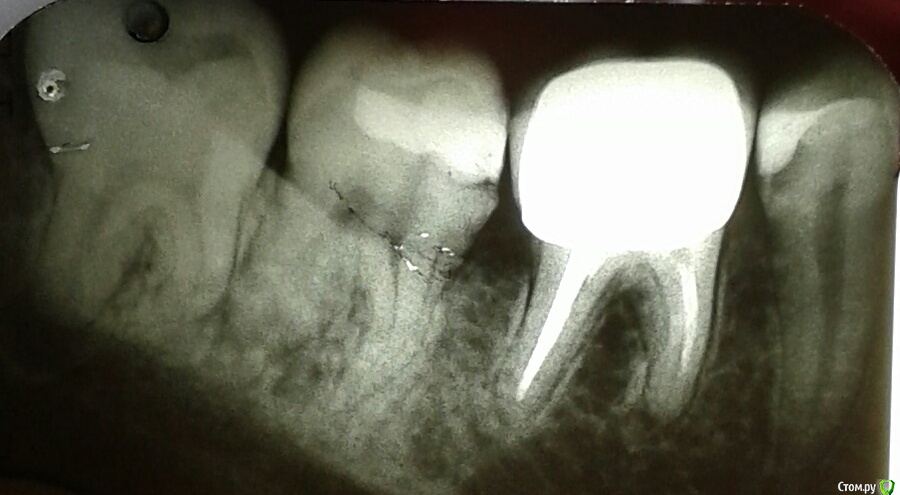

Инна2106 Опубликовано 27 июля, 2018 Поделиться Опубликовано 27 июля, 2018 (изменено) Добрый день.Прошу помочь определить в чем может быть причина ситуации с зубом которая длиться уже две недели.Началось все в ночь 13 августа проснулась от боли в одном участке нижней челюсти, именно не зубе, а челюсти, боль не острая, а тупая ноющая. Встала, походила все прошло. Весь день ничего не болело. В ночь все повторилось уже дважды просыпалась от боли, не определенного зуба, а низа левой челюсти. Для снятия боли достаточно было просто походить в течении 5 минут, все успокаивалось.На следующий день пошла к врачу, сделал снимок, осмотрел, сказал, что есть небольшая гранулема под шестым зубом под коронкой из-за не до конца запломбированного канала, но это как оказалось старая проблема, определялась еще на ортопанораме зимой. Но по его словам она не может давать такого рода болей. Ночью не спала вообще, четыре раза вставала от болей, причем стоило только принять горизонтальное положение и начиналась ноющая боль в нижней челюсти слева, и потом верхней челюсти слева. Суть в том что боли появлялись именно когда ложилась, не важно днем или ночью, пока ходишь, сидишь ничего не беспокоило. Снова поехала на прием к врачу, сделал много проб, и воздухом и нитью, подозревал трещину по снимку рядом в зубе под пломбой, но сказал нить не цепляется и не рвется значит ее нет, но вскрывать этот зуб не смысла так как на простукивание все было спокойно и сверху и снизу. Десна все розовые, кровоточивости нет. Через три дня поехала к другому врачу сделал свой снимок, предположил как вариант что восьмерка может двигать зубной ряд оттуда и боль, но сама восьмерка абсолютно спокойна, не болит, нет отечности десны. Его заключение, что причина в троичном нерве, а не в зубах. До этого по рекомендации первого врача принимала Азитромицин 3 дня и Нимесил не помогло. Начала пить Нейродикловит (диклофенак с витаминами группы В) и наконец-то начала ночью спать, но с понедельника 23 июля начал болеть зуб при накусывании рядом с коронкой (семерка), я на эту сторону и так не ем уже две недели, почувствовала боль при пережевывании пищи. когда верхних зуб попадал на нижний, попробовала постучать ложкой и ощутила боль в семерке снизу. В среду поехала к третьему врачу, он сделал пришлифовку семерки нижней с верхней так как нагрузка на зуб неправильно распределялась на одно сторону, порекомендовал попить Нимесил и наблюдать.Суть в том, что на данный момент исчезли боли в горизонтальном положении, но не могу жевать и есть нормально, сам зуб не болит, но если попробовать накусить слегка зубочистку на семерку появляется боль, отпускаешь проходит.Очень прошу помогите разобраться что это и как себе помочь, скоро нужно уезжать и не знаю стоит ли сейчас снимать коронку или все же причина не в этом зубе. Стоит ли делать КТ, новую ортопанораму, если по снимкам ничего не видят. Внизу прикрепила фрагмент ортопанорамы делала в феврале этого года, и нашла снимок этого сделанный в конце апреля прошлого года для сравнения.Заранее большое спасибо. Изменено 27 июля, 2018 пользователем Инна2106 Ссылка на комментарий

kramer Опубликовано 27 июля, 2018 Поделиться Опубликовано 27 июля, 2018 (изменено) Да банально пульпит нижней семерки. Там кариес под пломбой, видно же. Изменено 27 июля, 2018 пользователем kramer 1 Ссылка на комментарий

red_butler Опубликовано 27 июля, 2018 Поделиться Опубликовано 27 июля, 2018 Да банально пульпит нижней семерки. Там кариес под пломбой, видно же. тут кандидатов на пульпит прорва 2 Ссылка на комментарий

kramer Опубликовано 27 июля, 2018 Поделиться Опубликовано 27 июля, 2018 Про пульпит я у всех трех врачей с самого начала спрашивала, все его отрицают, так как нет реакции на холодное, горячее, воздух, зуб не болит все это время, появилась только реакция по накусывание и простукивание. По Вашему мнению нужно удалить нерв в семерке и боль пройдет? Как и сказано было выше, я насчитал с этой стороны 5 зубов, которые могут давать такую симптоматику, но из них 7ка наиболее вероятно. Ссылка на комментарий